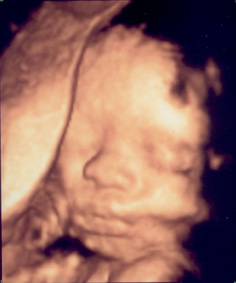

입체촘파!! 꺅 >.<

울 사랑이 입체촘파 ^^ setLayoutPhoto2Preview("free", "5", "0", "0", "http://blogfil...